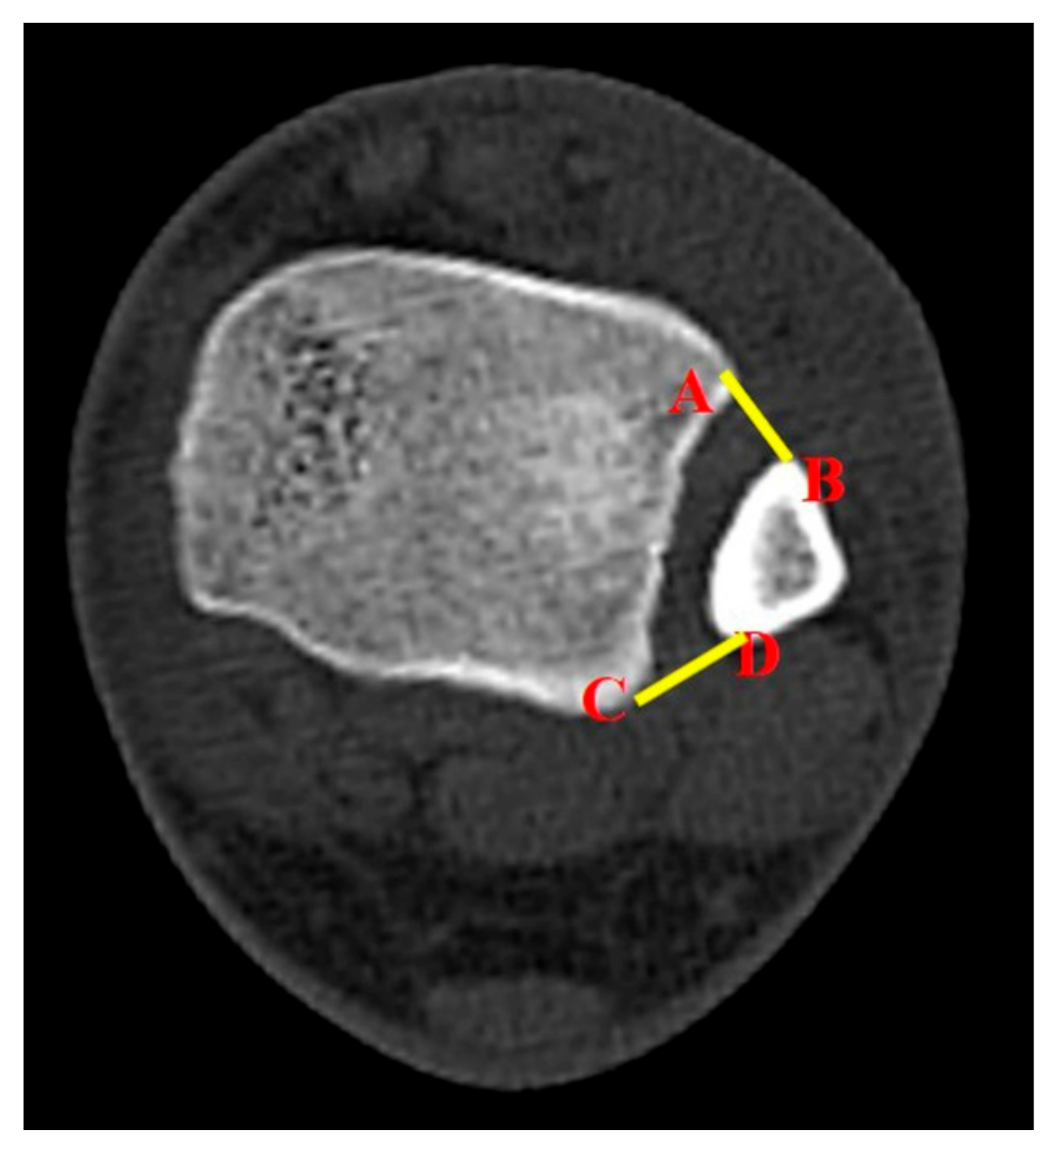

The study also utilized a new parameter to evaluate syndesmotic injuries. The surface area of syndesmosis (SAS) was measured 1.0 cm and 1.5 cm above the tibial plafond. From here, the researchers named them SAS 1.0 and SAS 1.5, respectively. The method for measurements of SAS 1.0 and SAS 1.5 was established by a consultative meeting made up of specialist in ankle joint trauma (SWL, CHP, BSK). The inferior border of the tibial plafond was first identified on the axial section and cross-referenced with the coronal section with scout imaging using CT scan. Each parameter (SAS 1.0 and SAS 1.5) was measured in the axial section of CT scan, which corresponds with the coronal section 1.0 cm and 1.5 cm above the tibial plafond (

Figure 2). If there is a fracture line in the area to be measured at fibular site, that area was included as fracture diastasis.

The introduction of SAS 1.0 was a trial to utilize the two-dimensional image information in evaluating ankle fractures with syndesmotic injuries. We speculated that a two-dimensional surface area would stand out with better spatial comprehension of anatomic structures between the tibia and the fibula. The SAS 1.0 was measured 1.0 cm above the tibial plafond, which represents the deepest part of the incisura fibulae, similar to previous studies that utilized axial CT scans [

9,

12,

13,

14]. When more than one transfixation between tibia and fibula is performed, the area 15 mm above it is commonly transfixed [